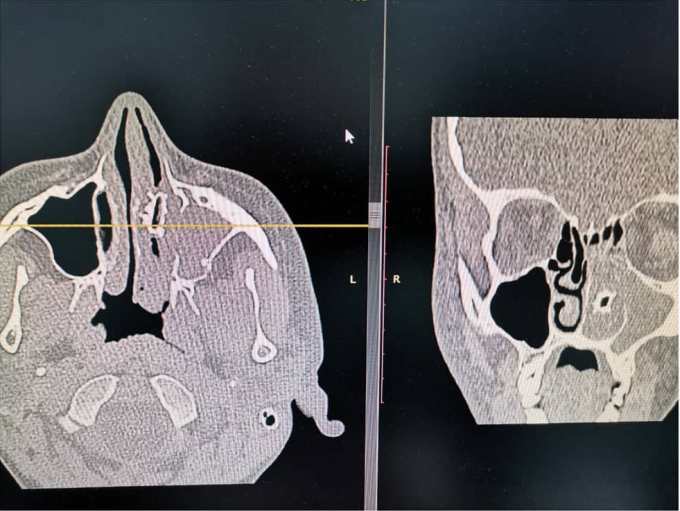

Женщина обратилась к медикам с жалобой на то, что ей трудно дышать. Ей сделали томографию головы, которая показала наличие инородного тела в полости носа.

Пациентке сделали операцию и вытащили из носа насекомое. Его направили на гистологию.